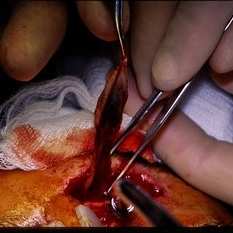

Jan 8 2015 by H. Michael Lambert, MD

Surgical view repairing scleral rupture.

Condition/keywords: trauma